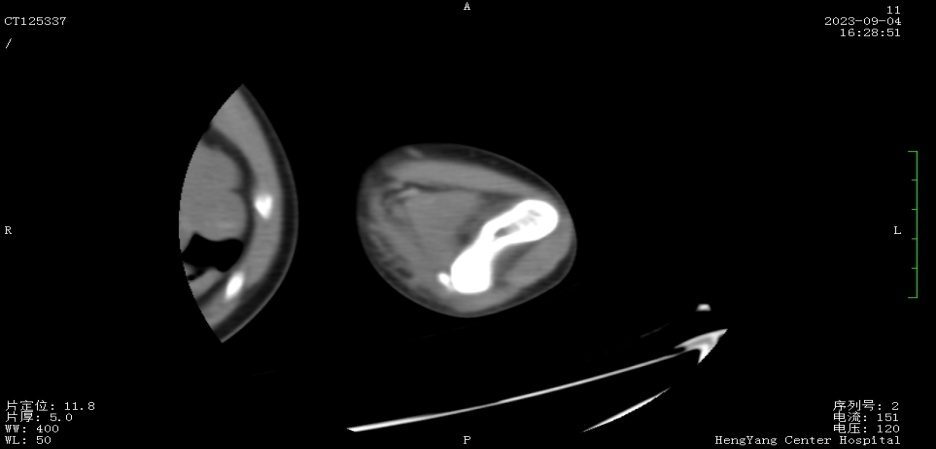

接診后,醫(yī)師發(fā)現(xiàn)小莫同學(xué)的左肘關(guān)節(jié)自然狀態(tài)下僅能伸展至約115°,并伴有習(xí)慣性屈肘。經(jīng)與骨科醫(yī)生溝通并閱片后,考慮骨化肌炎,針對這種情況,一般采取手法松解關(guān)節(jié)和關(guān)節(jié)功能鍛煉相結(jié)合的治療方案。但此方案常用于成人患者的關(guān)節(jié)粘連傳統(tǒng)松解術(shù)和關(guān)節(jié)松動(dòng)訓(xùn)練,對于兒童來說刺激強(qiáng)度太大,且因兒童骨骼及關(guān)節(jié)較成人脆弱,無法保證治療的連續(xù)性及安全性,若一味采取輕柔手法,不僅治療時(shí)間長、見效慢,還可能加重后續(xù)治療難度。